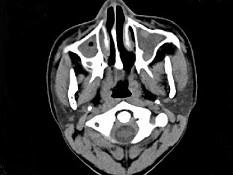

问题 男,14岁,持续性鼻塞、嗅觉减退,流脓涕数年,CT检查如图,最可能的诊断为 ( )

选项 A、恶性肉芽肿 B、上颌窦癌 C、鼻及鼻窦息肉 D、过敏性鼻炎及鼻窦炎 E、鼻炎及鼻窦炎

答案 E